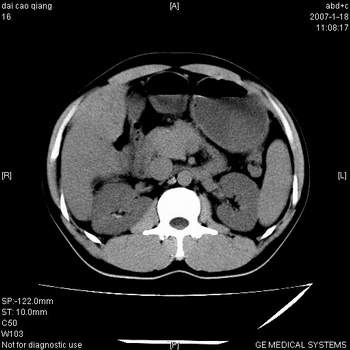

符合巨块型肝癌表现:

1、平扫低密度,增强后表现为快进快出。

2、动脉期可见迂曲的动脉供血血管

3、并可见门静脉右支癌栓形成

4、可见假包膜

5、腹主动脉旁结节影,考虑肿大淋巴结。

肝右叶巨大不均匀低密度肿块,前缘有假包膜,增强明显的呈快进快出表现,门脉右支有癌栓,病人虽然年轻但还是首先考虑肝右叶巨块形肝癌,病人血象高只能说有合并感染。不支持肝脓肿。